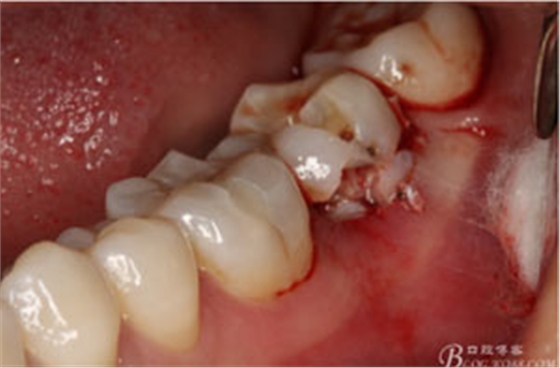

圖6.微創(chuàng)挺拔除37.

圖7.37牙冠碎裂。多生牙壓迫吸收程度嚴(yán)重。

圖8.拔除的37頰側(cè)的牙根完全被壓迫吸收完

圖9.清理牙槽窩過后。多生牙的牙冠暴露在牙槽窩內(nèi)。